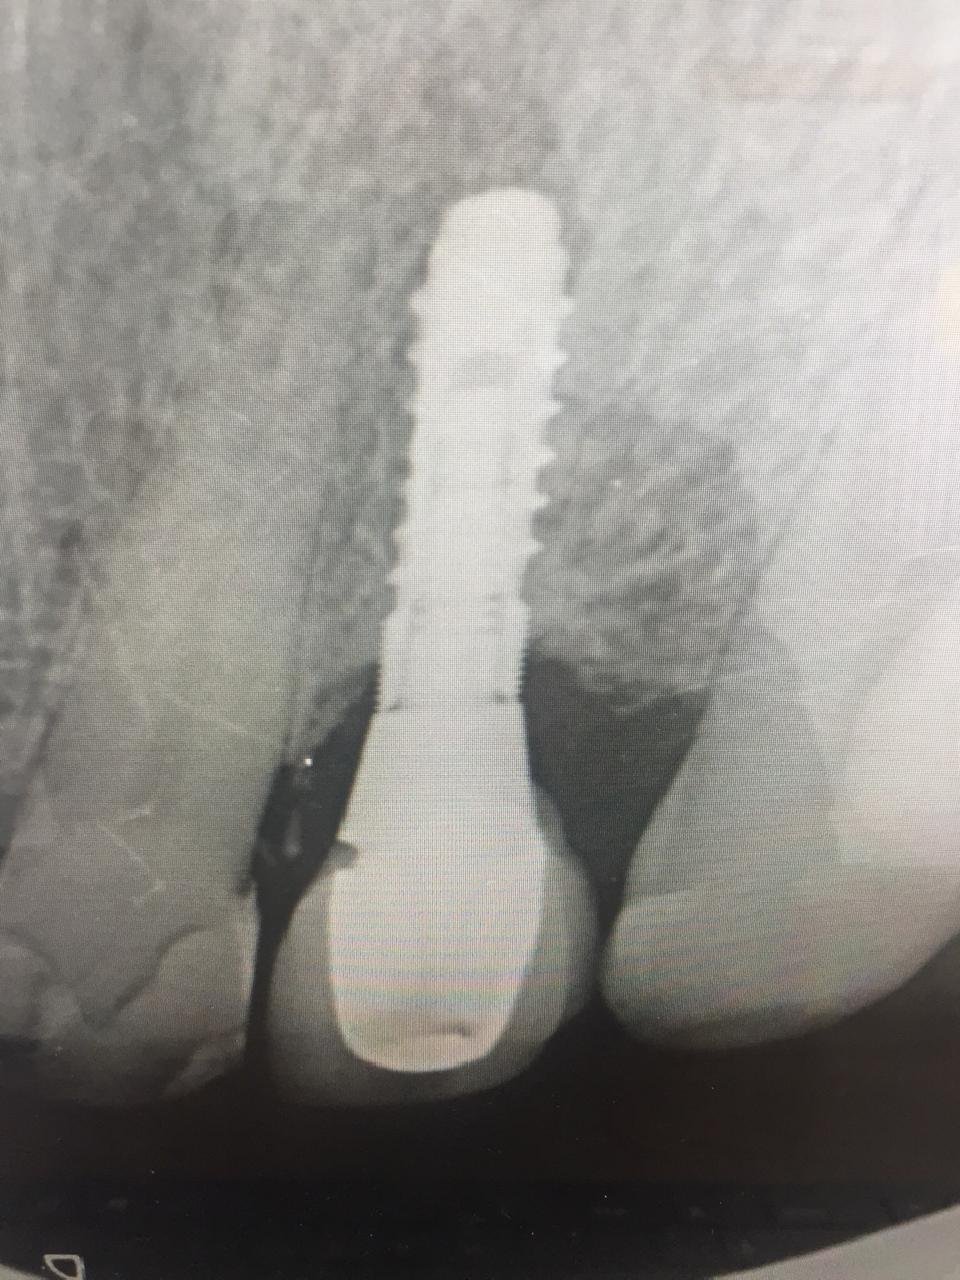

Buenas, Tengo este caso, la corona del 46 la vamos a cambiar, pero no conozco la marca de implante. También presenta movilidad, pero con los destornilladores de 1,20 no logro apretarla. [...]

Quiero apretar O retirar protesis con movimiento pero ningún destornillador que tengo funciona podrían decirme que implante es? Y que tipo de conexión tiene el tornillo?

se ha fracturado el tornillo, necesito identificar

Buenas grupo, el dentista me envia este implante al cual no tiene ni idea de cual es al igual que yo tampoco. Es conexion externa y es parecido a branemarck [...]

Necesitaría saber la marca de los implantes 3.6 y 3.7. Viene de una clínica que ha cerrado y la paciente no tiene nada de información. Son de conexión externa. Adjunto [...]